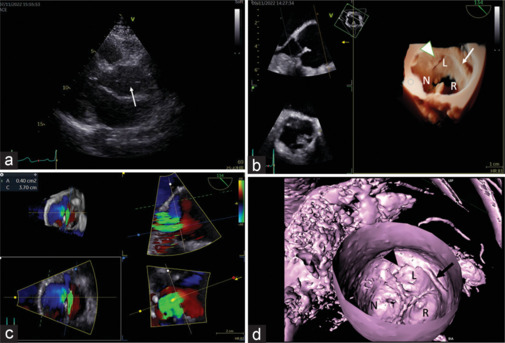

A 53-year-old woman was evaluated for left ventricular hypertrophy. Transthoracic echocardiography showed a mobile linear density in the ascending aorta and eccentric aortic insufficiency, raising the concern of aortic dissection. Transesophageal echocardiography and cardiac computed tomography (CT) found complex bands of tissue extending from the commissure to the aortic wall, confirming aortic valve tendon. It is an extremely rare malformation of aortic valve associated with aortic regurgitation that mimics aortic dissection. Although preoperative diagnosis has been challenging, three-dimensional echocardiography and CT reformatting aided the visualization of the spatially complex structure.